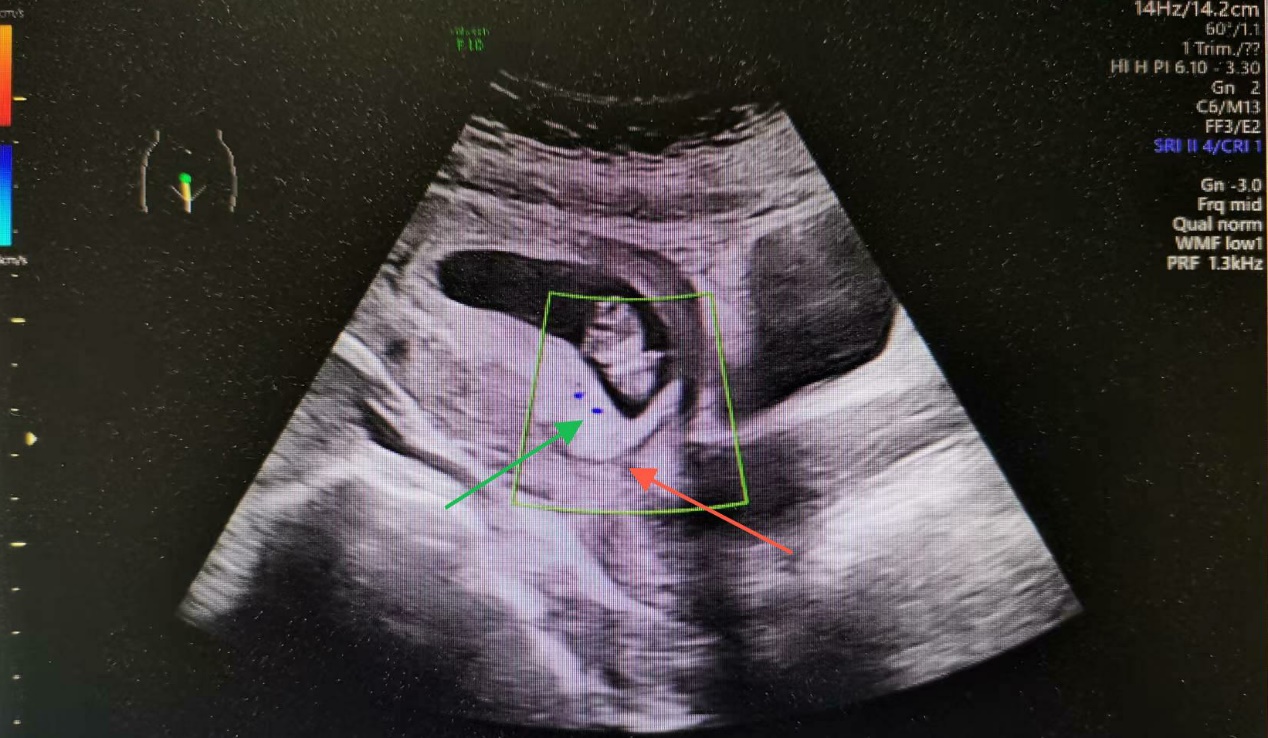

据统计在早孕期约20%-50%胎盘覆盖或毗邻子宫颈内口。如图1超声在早期产前筛查时可以观察胎盘,一般会描述其位置,在前壁、后壁还是宫底,在超声图1中胎盘位于后壁,覆盖宫颈内口。此图可以为整个孕期胎盘定位及临床急症处理时做参考。

图1 绿色箭头:覆盖宫颈内口的后壁胎盘;红色箭头:宫颈内口